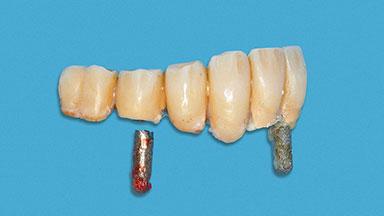

A 93-year-old female patient presented in September 2010 with an enlarged swelling on the lingual side of her lower incisors. At the time, she was essentially healthy, except for reduced vision due to bilateral age-related macular degeneration. She had been a heavy smoker (about 30 cigarettes a day) for the past 20 years after becoming a widow. The patient lived at home by herself, with full-time domestic support. An extraoral examination revealed nothing adverse. Intraoral plaque control was anything but ideal, and a soft-tissue tumescence was visible around the lingual aspect of 41–42. Because the nature of the lesion was not clear, a biopsy was carried out that revealed the inflammatory nature of the lesion. The panoramic radiograph showed six irregularly distributed mandibular implants supporting a full-arch prosthesis, with various degrees of interproximal peri-implant resorption. The periapical radiograph revealed interproximal bone resorption mesially and distally to implant 41.

# of Implants 2

Type of Implants One-Piece

Attachment One-Piece

Prosthesis Type FDP